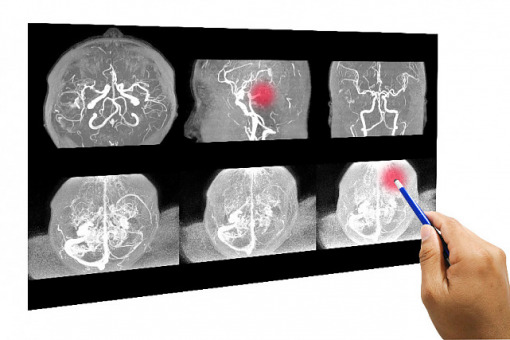

Neurolodzy z WIM wykonali trombektomię mechaniczną u 13-latka

Lekarze z WIM w Warszawie przeprowadzili zabieg leczenia ostrego udaru mózgu u trzynastoletniego dziecka. Operacja odbyła się z wykorzystaniem trombektomii mechanicznej. Dotychczas nie opracowano jednak wytycznych co do zasad leczenia zabiegowego, opieki anestezjologicznej i neurologicznej dzieci z udarem mózgu.

Jak dodano, lekarze działali w sytuacji niestandardowej ze względu na brak istniejących wytycznych co do zasad leczenia zabiegowego, opieki anestezjologicznej i neurologicznej dzieci z udarem mózgu. Na stronie WIM zaznaczono, że jest to drugi lub trzeci udokumentowany przypadek leczenia zabiegowego udaru u dziecka w Polsce. Zoperowany chłopiec jest także najmłodszym pacjentem poddanym trombektomii w naszym kraju.